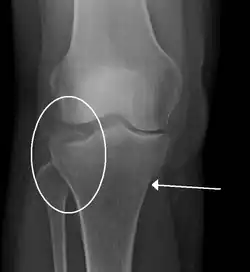

- Bumper fracture - a fracture of the lateral tibial plateau caused by a forced valgus applied to the knee

- Segond fracture - an avulsion fracture of the lateral tibial condyle